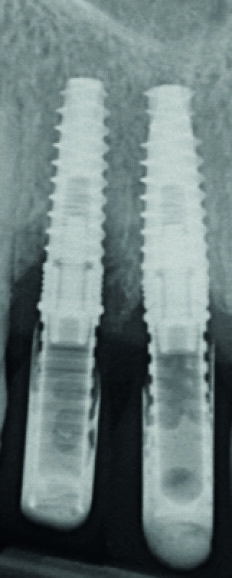

Fig. 7 : Radiographie « long-cône » postopératoire. Notez l’image résiduelle de l’alvéole au niveau de l’implant en 12.

Notez aussi la très bonne cicatrisation osseuse péri-implantaire surtout en 12 (comparaison possible avec la figure 7).

L’intervention est programmée en février 2019. Des implants de type Avinent Ocean hexagone interne sont poses. Afin de sécuriser la pose des implants et assurer l’assainissement du site, un lambeau est réalisé après l’extraction des deux dents. Toute la séquence de forage ainsi que la pose des implants sont passés à travers les douilles du guide chirurgical. L’indexation doit être bien respectée en alignant les repères présents sur le guide avec ceux du porte implant.

Les implants sont vissés à la main à l’aide d’une clé dynamométrique. Nous vissons ensuite les piliers temporaires (Avinent), et les couronnes provisoires en résine PMMA sont rebasées et scellées (laboratoire Crown Ceram) avant de suturer le lambeau. À ce stade, notons que le second avantage du lambeau est de pouvoir aussi contrôler parfaitement l’adaptation prothétique, et d’éviter toute fusée de ciment de scellement. Une radio de contrôle postopératoire est réalisée (Fig. 7).

La patiente est revue à huit jours. Les suites opératoires se sont bien passées et la prise d’antalgique très limitée. Les sutures sont retirées. Puis la patiente est revue en contrôle à deux mois (Fig. 8), trois mois (Fig. 9) et quatre mois. Les radiographies de contrôles montrent un gain osseux au niveau de l’implant en 12 et une parfaite intégration des deux implants. Les cicatrisations clinique et osseuse sont très bonnes et il est décidé de passer à la prothèse définitive. Les couronnes et piliers provisoires sont retirés et les tissus mous vérifiés (Fig. 10).